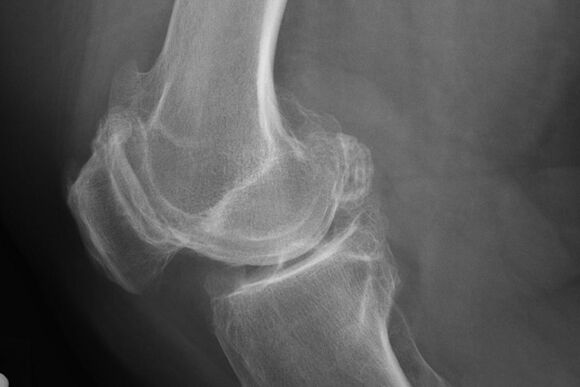

Di norma, la diagnosi della malattia in questa fase si verifica per caso, durante un raggio x. Su di esso, il medico può notare alcune irregolarità sulla cartilagine. È anche possibile restringere il lume tra le parti dell'articolazione.

X -Ray aiuterà a identificare le deviazioni nella cartilagine.

Dopo l'esame, il medico prescrive la radiografia del paziente. Questo è il metodo principale per diagnosticare l'artrosi dell'articolazione del ginocchio di qualsiasi grado.

X -Ray dà al medico un'idea dei cambiamenti che si verificano nella cartilagine dell'articolazione. Tuttavia, in alcuni casi, la fase iniziale potrebbe non essere definita nella foto.

Se necessario, il medico può prescrivere un passaggio ripetuto di una tomografia a raggi X o calcolata e risonanza magnetica.